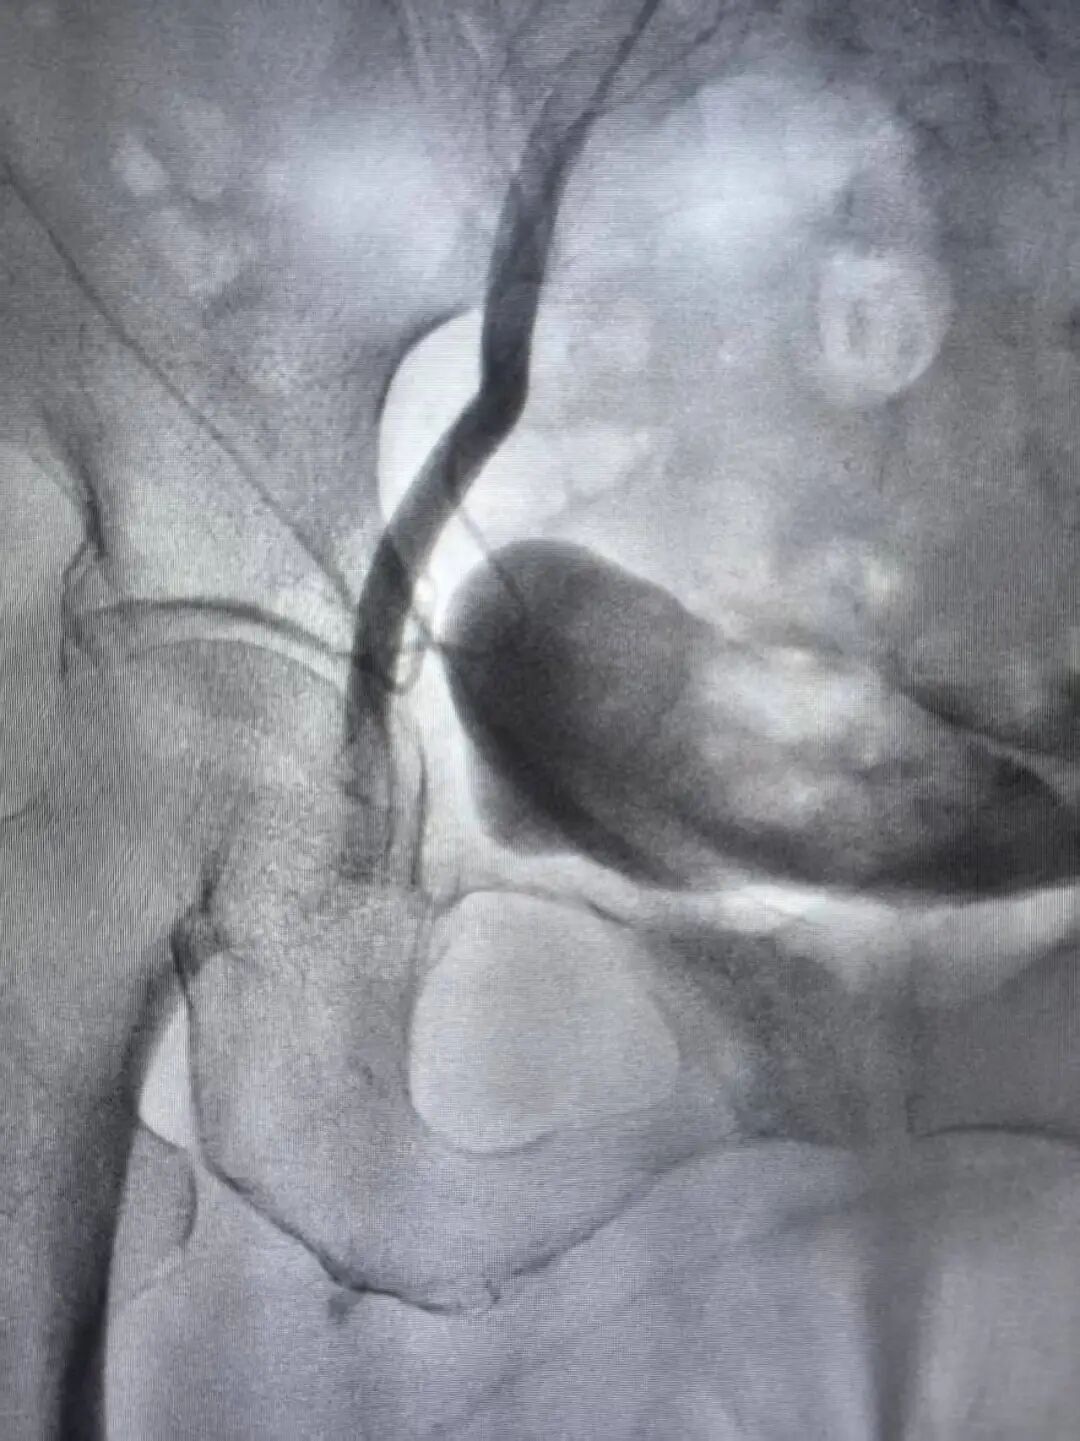

(右侧股总动脉栓塞)

“马上启动多学科协作!”急诊科立即联系介入及脑血管病科薄进保主任。医护团队在最短时间内完成术前准备,患者从急诊室直接推入介入手术室,全程无缝衔接。急诊科护士寸步不离,密切监测心率、血压、血氧;介入团队早已就位,薄主任为孙奶奶实施右下肢动脉血栓取栓术